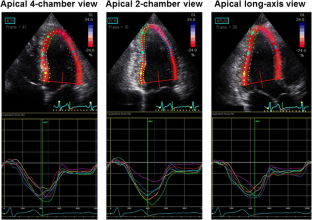

Fig. 1

Fig. 2